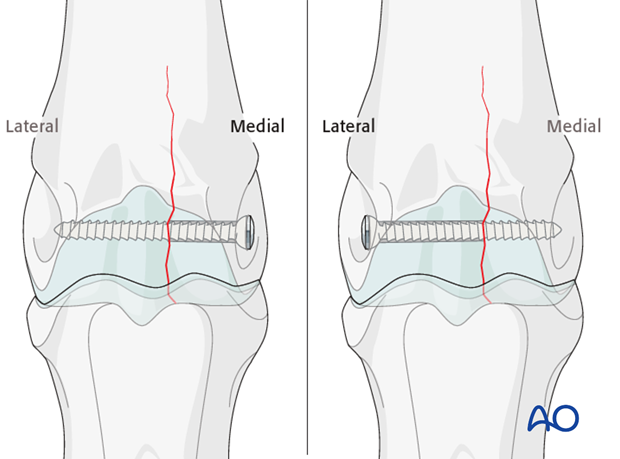

Although the glide hole is typically drilled through the smaller fragment and the thread hole across the larger fragment, this particular fracture is often repaired in the opposite manner. The major reason is that it is much safer and easier to approach the leg from the lateral side than the medial side. Fortunately, medial condylar fractures tend to be close to the midline so there is little difference between the width of the two fragments. The bone in this location is so strong that 25 mm of thread engaged with a 4.5 mm cortex screw is already exceeding the strength of the screw. Therefore, strong fixation can be achieved even though the repair is called “backward” or “reverse” lag screw.

A second screw is placed approximately 2 cm proximal to the first screw.

Additional screws may be added according to the radiographically visible length of the fracture. In standing horses, however, most surgeons place only 2-3 screws.

NEVER place a screw where you cannot clearly see the fracture line.